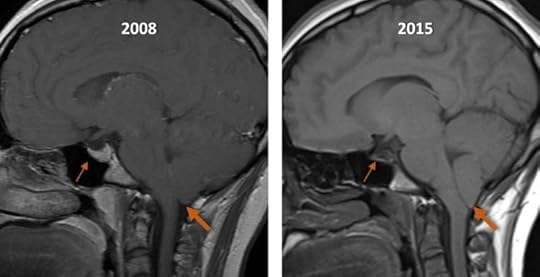

As an example, the figure below shows a patient with undiagnosed IIH imaged in 2008 (left image) whose chronically elevated ICP on re-imaging in 2015 (right image) resulted in increasing tonsillar ectopia (large arrow) as well as an increasingly “empty” sella turcica (small arrows). The appearance in 2015 could have easily been misdiagnosed as a Chiari 1 malformation.

A second problematic imaging finding is that of cerebellar tonsillar ectopia. This appearance of the cerebellar tonsils extending further below the foramen magnum than expected may be due to a variety of innate, congenitally abnormal, or ICP-related conditions. It is important to keep in mind that there is variability in the appearance of nearly all anatomic structures, and that in some people the cerebellar tonsils may have simply developed lower than usual, if they maintain a normal rounded morphology. This is to be distinguished from a Chiari 1 malformation where the tonsils are low-lying and “peg-like” in morphology and may be associated with other findings such as a spinal cord syrinx. IIH can also result in cerebellar tonsillar ectopia presumably due to the increased ICP pushing brain structures downward, as can SIH due to loss of the buoyancy from CSF causing a “sagging” appearance of the brain. It is critically important to differentiate each of these diagnoses, as the management is substantially different.